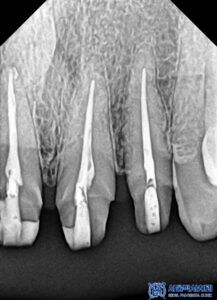

제거를 하고 확인해 보니,

내부로 충치가 생긴 것을

확인할 수 있었습니다.

충치를 제거하고

신경치료를 시작하였습니다.

본원에서는

MTA 신경치료를

진행하고 있습니다.